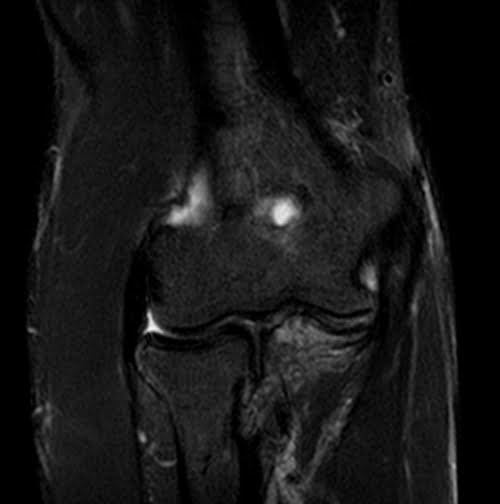

mri elbow coronal stir image 3 - MRI